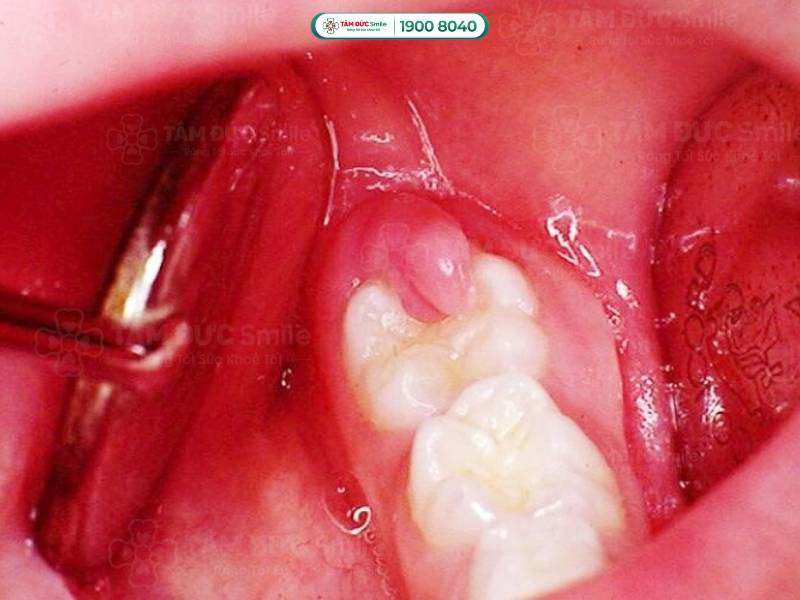

Bị áp xe răng ở vị trí răng số 7

- Mô nướu sưng và chứa đầy mủ. Phần lợi bị sưng to, nhìn như mọc cái mụn ngay cạnh răng hàm.

- Khi bọc mủ bị vỡ sẽ tạo ra các "lỗ rò" để giải phóng mủ bên trong. Lúc này, bạn thấy được phần nướu sưng tấy đặc trưng của tình trạng nhiễm trùng.